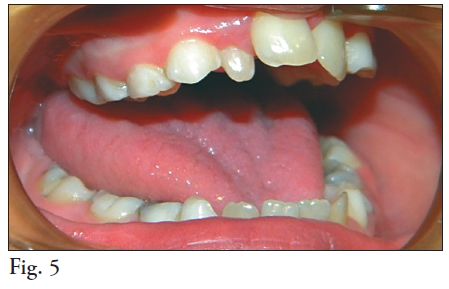

5. MORFOLOGÍA DENTARIA

El Síndrome de Down está asociado con alteraciones en la morfología dentaria, las coronas son cortas y pequeñas (microdoncia) al igual que las raíces, presentando además frecuentemente raíces fusionadas tanto en molares superiores como inferiores (44, 47) lo que reduce la superfi cie del periodonto profundo favoreciendo la movilidad y la pérdida dentaria con reabsorciones óseas no tan avanzadas. (Fig. 5) En un grupo de 49 pacientes estudiados en Brasil, (2007) cuyas edades oscilaron entre 3 y 33 años se encontró que el Taurodontismo fue la anomalía dental más frecuente (85,71%), anodoncia en 34,69%, dientes cónicos en 14,28% y 2,04% presentó fusión y microdoncia (48)